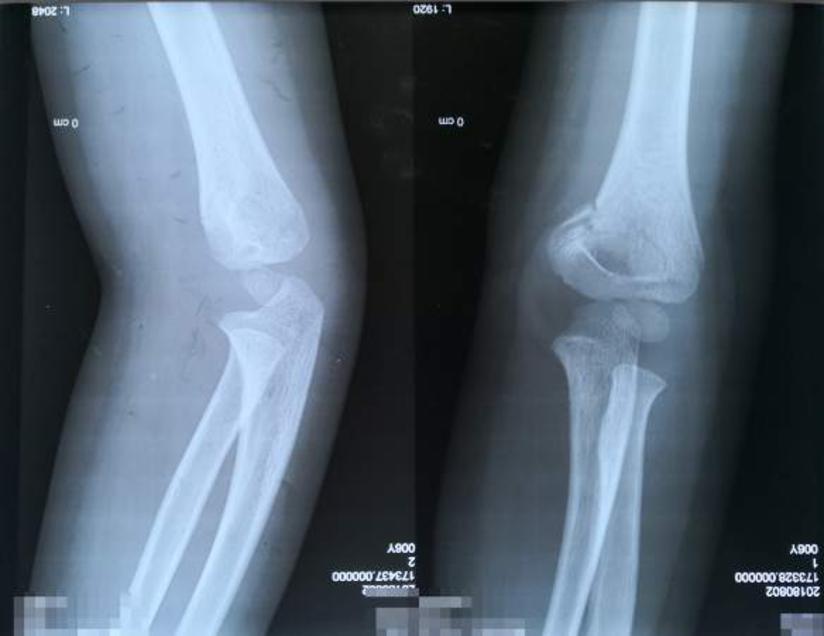

鹰嘴骨折 肘部骨折 疾病 21

尺骨鹰嘴骨折固定 克氏针还是cable Pin Medsci

鷹嘴突症候群 常見的肘部骨折 桃園振雄診所